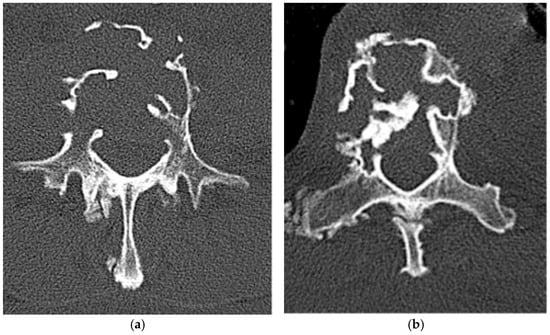

Ewing Sarcoma